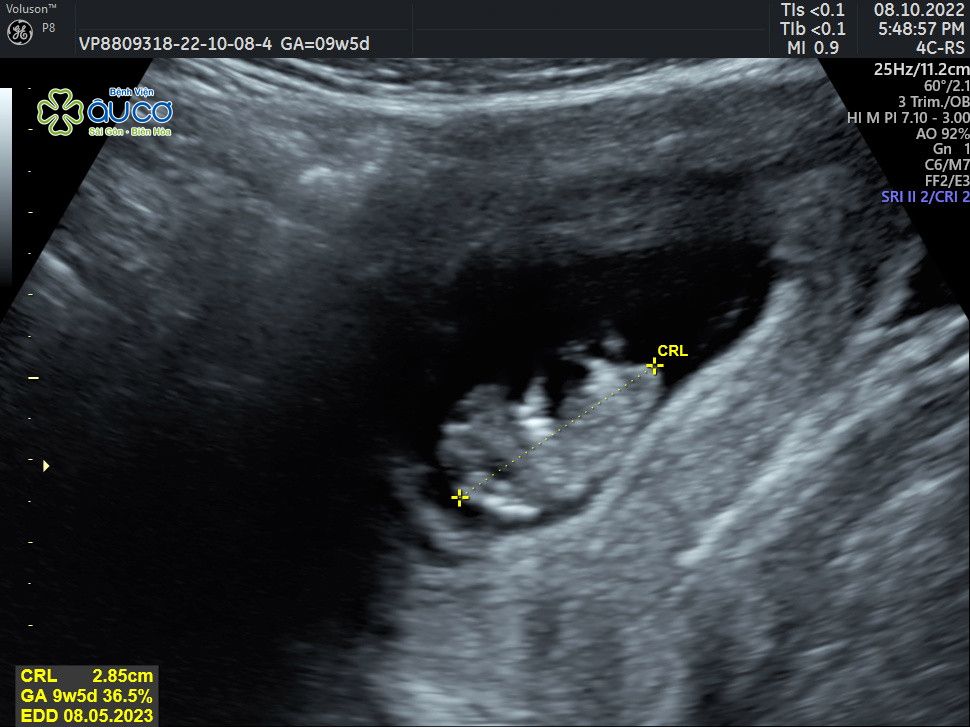

* Những hình ảnh siêu âm đáng yêu nhưng không kém phần nghịch ngợm của con qua các mốc thời gian:

| 9 tuần 5 ngày |

![]() |